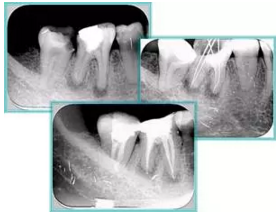

6. 鈣化

常見有修復(fù)性鈣化和增齡性鈣化。下面為根管鈣化 X 線片。

7. 器械折斷

右圖及下圖為器械折斷的 X 線片。箭頭處示折斷器械。

解決方法:

( 1 )取出。

( 2 )通過。

( 3 )重新確定工作長度,充填。

( 4 )根尖手術(shù)。

器械折斷可以不用取出,取出的原因多是患者心理因素。留在里面的器械關(guān)鍵是進(jìn)行消毒,預(yù)防性使用抗感染藥物,預(yù)防感染。

二、臺階

定義:根管內(nèi)壁上人為產(chǎn)生的不規(guī)則形狀阻止器械順利進(jìn)入根尖。

原因:器械沒有預(yù)彎,根向壓力過大。

右圖箭頭處示臺階形成。